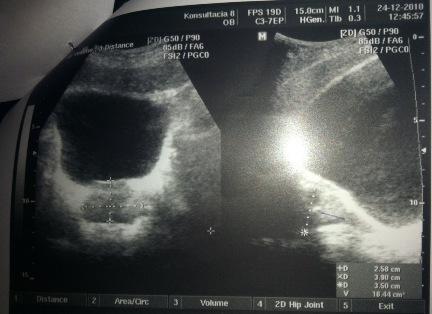

Добрый день! Дайте совет пожалуйста! Мне 30 лет. В декабре 2010 г. обнаружен хронический простатит, сделана узи, назначено лечение :

Псоле второго раза было сделано УЗИ, обнаружено образование камней.